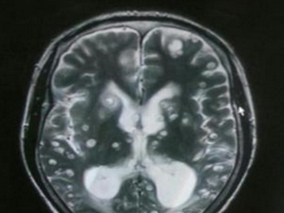

脑囊虫病诊断:钆双胺-MRI脑室造影能提高诊断准确性

1小时条评论脑囊虫病是由寄生虫(猪绦虫为主)所传染的一种顽固性颅脑内疾病。2015年7月,发表在《Trop Med Int Health.》一项研究目的是评估钆双胺(GDD)-MRI脑室造影在鉴定脑囊虫病病例中的诊断价值。结果表明,钆双胺-MR...